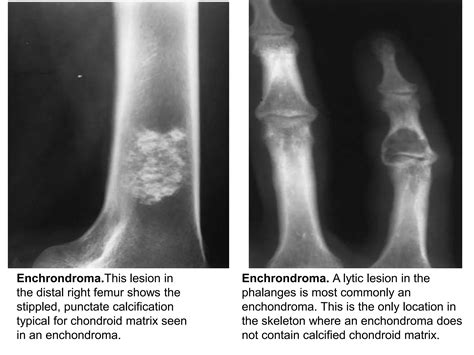

Discover the causes, symptoms, and diagnostic process for lytic bone lesions. Our expert guide explores how these areas of bone destruction appear on imaging, the difference between benign and malignant tumors, and essential treatment options. Learn to identify the warning signs of skeletal abnormalities and understand when to consult a specialist for comprehensive bone health evaluation and care.